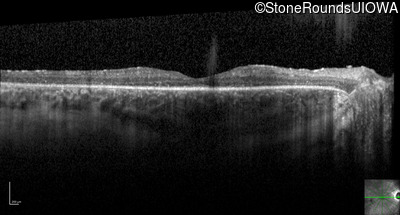

Optical Coherence Tomography - Right - 20/50

Exemplar / OCT Stack

OCT Stack